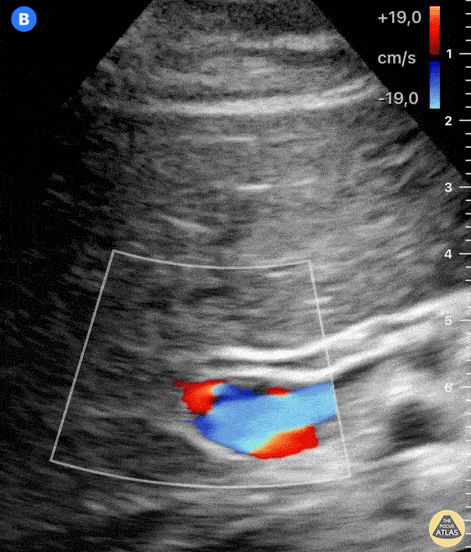

Often, a left lateral position delivers a clear image of the common bile duct (CBD) on its entire length, as is the case in this clip. Notice the normal hyperechoic walls and its small diameter. The CBD inner wall diameter should be < 6 mm in healthy adults, although it can be enlarged in post-cholecystectomy patients. Dr. Felipe Urriola P. Emergency Unit, Puerto Aysen Hospital. Chilean Patagonia.